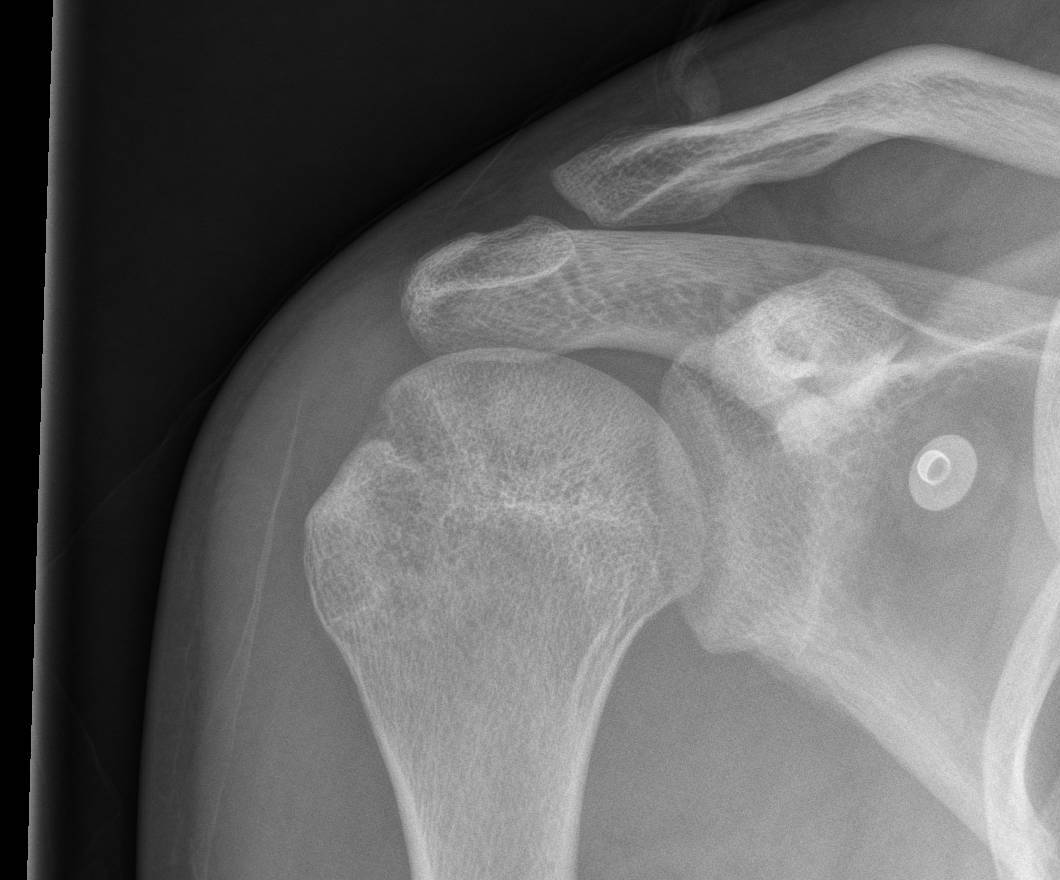

Xray

Bony bankart

Hill Sachs